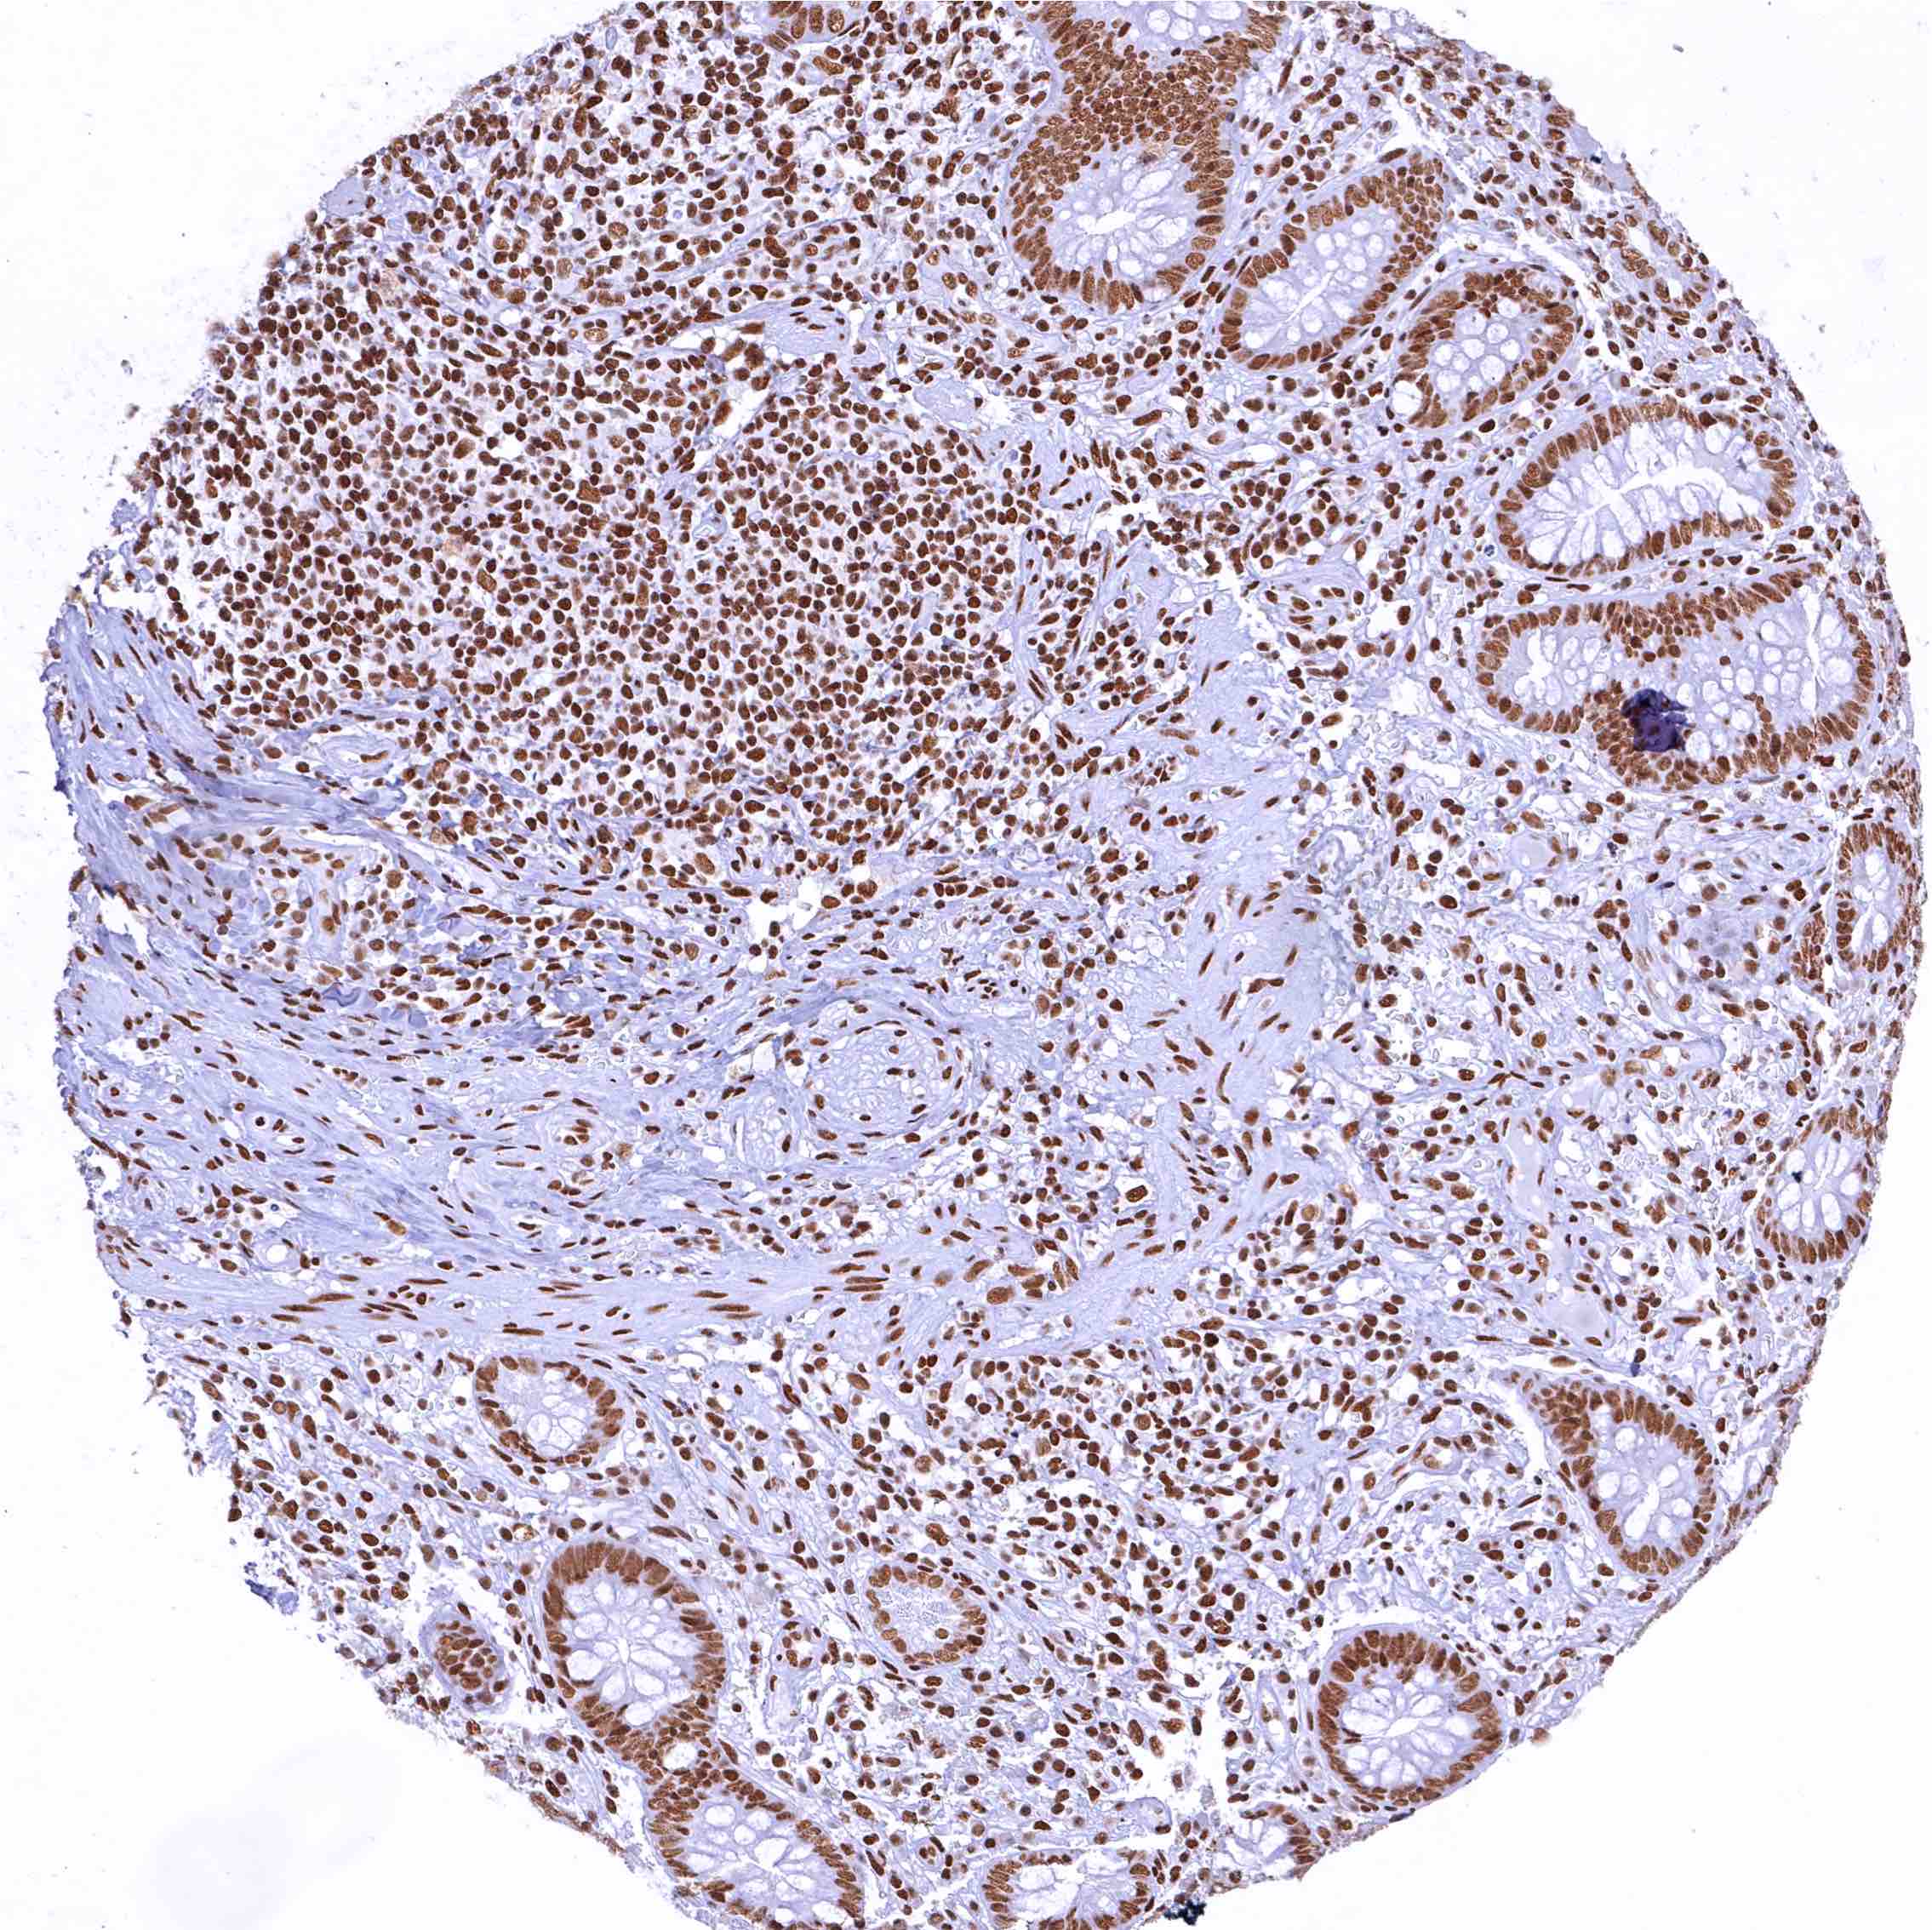

Rectum, mucosa – In colonic epithelium, the CBP staining intensity decreases slightly from the crypt base to the surface epithelium